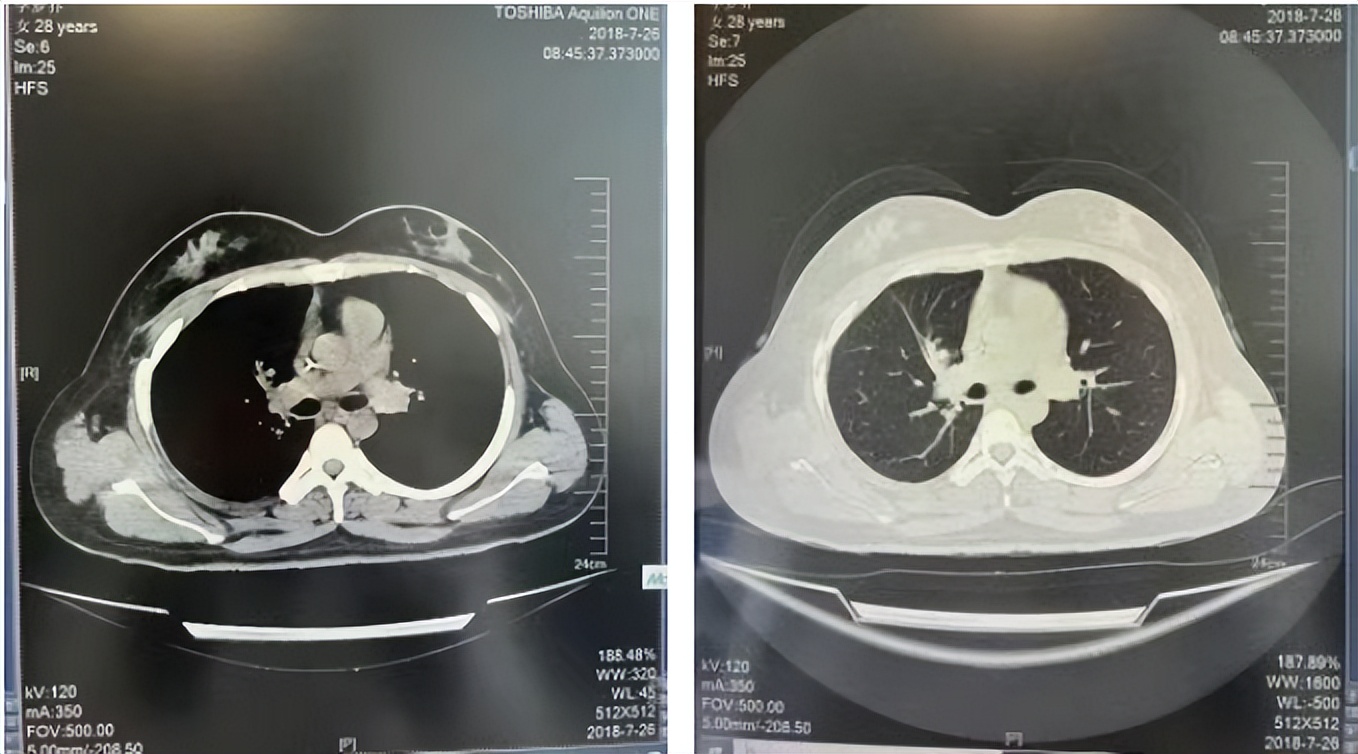

56岁,女性,无吸烟史饮酒史,既往体健。2023年02月患者体检发现肺占位性病变,胸部增强CT:右肺下叶后基底段结节;右侧锁骨上及纵隔内多发淋巴结肿大。PET-CT:右肺下叶周围型肺癌可能性大;1R、2L、3P、4R、4L及7组淋巴结转移可能性大。2023年02月就诊于本院胸外科行超声胃镜下纵隔肿物穿刺活检术,病理:结合免疫组化,符合肺腺癌。行NGS基因检测:EML4:exon20-ALK:exon20融合。PD-L1(克隆号22C3)TPS=55%。

2023年2月20日基线检查